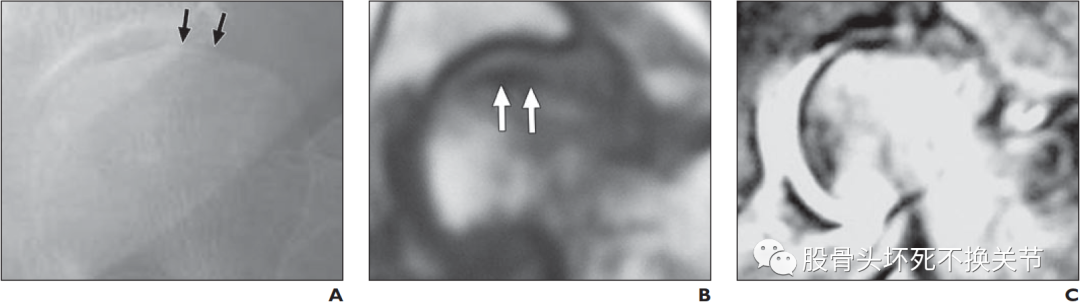

图a. 右股骨头蛙位X线片:股骨头前外侧软骨下高透明区(箭头)。图b. 股骨头冠状切面X线照片显示软骨下骨折(箭头所示),表现为新月征。注意:软骨下松质骨小梁的碎裂和压实,削弱了关节表面。肱骨头坏死的新月征:

根据T1加权MRI(冠状面)上条状低信号带的形状,区分骨坏死和软骨下不全骨折的标准图。

A. 在骨坏死中,低信号带是光滑的,向关节面凹陷

B. 软骨下不全骨折,低信号带不规则,凸向关节面